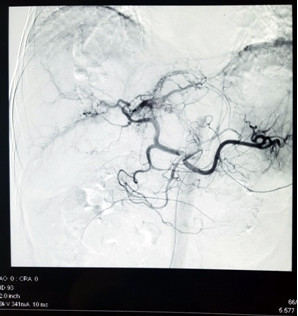

Các bác sĩ Bệnh viện Ung Bướu Hà Nội vừa thực hiện thành công ca cấp cứu u gan vỡ gây mất máu cấp, có nguy cơ tử vong cao nếu không được can thiệp kịp thời. Bệnh nhân được cầm máu bằng phương pháp nút tắc động mạch gan, giúp vượt qua “cửa tử”. Bệnh nhân Ngô Văn S., 59 tuổi, trú tại Hoàng Mai – Hà Nội mắc ung thư gan, khối u có đường kính 6 cm, lồi khỏi mặt dưới gan trái, đã được nút mạch hóa chất cách đây 3 tháng, sức khỏe ổn định. Đến sáng chủ nhật ngày 8/12/2019, bệnh nhân được người nhà đưa đến Bệnh viện Ung Bướu Hà Nội trong tình trạng đau bụng dữ dội vùng thượng vị, hoa mắt chóng mặt, da nhợt nhạt, mạch nhanh 140 lần/phút, huyết áp tụt còn 90/70 mmHg. Qua siêu âm, các bác sĩ phát hiện có nhiều máu trong ổ bụng bệnh nhân. Kết quả chụp cắt lớp vi tính cho thấy, khối u gan kích thước hơn 6 cm thâm nhiễm nhu mô gan trái đã vỡ, còn đang có dấu hiệu chảy máu, tạo khối máu tụ lớn khoang hậu cung mạc nối, nhiều dịch máu quanh gan và tiểu khung, chỗ dày nhất 6 cm. Bệnh nhân được chẩn đoán sốc mất máu do u gan vỡ, nguy cơ tử vong cao. Trước tình huống nguy kịch của bệnh nhân, BSCKII. Nguyễn Đình Hướng – Trưởng Khoa Chẩn đoán hình ảnh đã hội chẩn cấp cứu và quyết định thực hiện kỹ thuật nút tắc động mạch gan để cầm máu u gan vỡ trên hệ thống máy chụp mạch số hóa xóa nền (DSA). Các bác sĩ khoa Chẩn đoán hình ảnh, Phẫu thuật – Gây mê Hồi sức đã khẩn trương sắp xếp hệ thống và tiến hành thủ thuật nhanh nhất có thể để “chạy đua” với “tử thần”. Cụ ông vỡ u gan, máu tràn ngập ổ bụng mà không hề biết ảnh 1Hình ảnh khối u gan hạ phân thùy IV bị vỡ gây khối máu tụ lớn quanh gan trái Bác sĩ Hướng cho biết: “Nếu không được xử trí ngay, bệnh nhân sẽ bị mất máu ồ ạt trong ổ bụng dẫn đến tử vong chỉ trong thời gian ngắn. Nút mạch gan là chỉ định hàng đầu để xử trí trong trường hợp này nhằm cứu sống bệnh nhân. Kỹ thuật can thiệp nút mạch sẽ bít tắc được mạch máu bị vỡ (nguyên nhân chảy máu), giúp bệnh nhân cầm máu tức thì, tránh nguy cơ tử vong. Hơn nữa, vị trí luồn thiết bị can thiệp kích thước nhỏ như vết tiêm truyền mạch máu, ít gây đau đớn, không để lại sẹo và thời gian hồi phục sức khỏe sau thủ thuật của bệnh nhân nhanh, ít tai biến so với các phương pháp điều trị khác.” Cụ ông vỡ u gan, máu tràn ngập ổ bụng mà không hề biết ảnh 2Hình ảnh động mạch thân tạng chụp bằng máy chụp mạch số hóa xóa nền: động mạch gan trái và phải còn đang có dấu hiệu chảy máu ra ngoài gan. Ca phẫu thuật diễn ra trong khoảng 30 phút. Sau khi nút tắc động mạch mạch gan, huyết động của bệnh nhân ổn định ngay. Huyết áp tăng lên 110/70 mmHg, mạch đo được 100 lần/phút. Theo dõi sau 1 tuần, mạch và huyết áp đều ổn định, chụp cắt lớp vi tính kiểm tra lại thấy động mạch gan trái và phải tắc hoàn toàn, khối u không còn tăng sinh mạch, không còn dấu hiệu chảy máu ra ngoài khối u, lượng máu tụ trong ổ bụng đã giảm 50%. Trải qua cơn “thập tử nhất sinh”, ông Ngô Văn S. chia sẻ: “Lúc vào viện tôi đau bụng quằn quại, cứ nghĩ mình sắp chết đến nơi. Rất may, tôi đã được các bác sĩ đưa đi cấp cứu rất nhanh, kịp thời cứu sống. Giờ sức khỏe tôi đã ổn hơn nhiều, ăn uống tốt rồi.” Cụ ông vỡ u gan, máu tràn ngập ổ bụng mà không hề biết ảnh 3Bệnh nhân S. tươi tỉnh sau 1 tuần được phẫu thuật cấp cứu Chụp và nút động mạch dưới máy chụp mạch số hóa xóa nền là kỹ thuật hiện đại trong điều trị bệnh lý khối u khi không có chỉ định can thiệp bằng phẫu thuật hoặc tiến hành trước phẫu thuật để tạo thuận lợi tránh các biến chứng chảy máu trong cuộc mổ cho bệnh nhân, mang lại nhiều cơ hội cứu sống người bệnh ung thư, nhất là ung thư gan. Đây là kỹ thuật nút mạch cấp cứu tương đối phức tạp, đòi hỏi bác sĩ điện quang can thiệp phải có kinh nghiệm và kĩ năng chuyên sâu, bài bản, trang thiết bị - vật tư y tế hiện đại đầy đủ và đồng bộ sẽ giúp bệnh nhân tránh được ca đại phẫu với thời gian nằm viện điều trị dài ngày, nguy cơ tử vong do mất máu và các biến chứng hậu phẫu. Kỹ thuật này ưu việt hơn rất nhiều so với trước đây, để điều trị u gan vỡ chảy máu cấp ổ bụng, bệnh nhân phải trải qua cuộc đại phẫu nặng nề, mất máu, vết mổ hở gây đau đớn, thời gian nằm viện kéo dài, tai biến trong cuộc mổ cũng như hậu phẫu phức tạp, hay gặp hơn. Kỹ thuật điện quang can thiệp đã được thực hiện thường quy từ nhiều năm nay tại Bệnh viện Ung Bướu Hà Nội, áp dụng cho rất nhiều các bệnh lý của các cơ quan bộ phận khác nhau như: u gan, u xơ tử cung, các u máu hàm mặt, các u máu phần mềm, các can thiệp tiết niệu và đường mật .... và rất nhiều các bệnh lý khác giúp bệnh nhân tránh được các cuộc đại phẫu nguy hiểm, nâng cao tỉ lệ cứu sống người bệnh, giảm chi phí và thời gian nằm viện. Quảng An #u gan #nút tắc động mạch gan